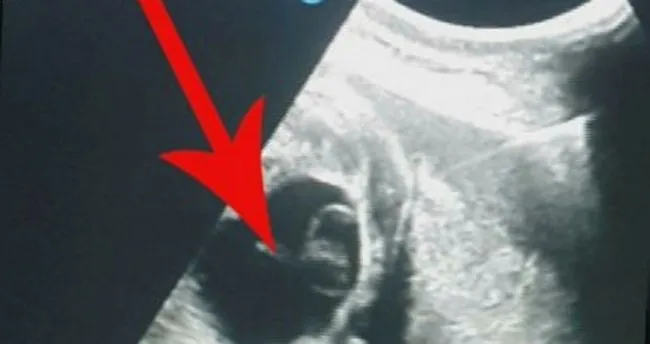

Yumurtalık kisti yumurtalıkların içerisinde ki sıvı dolu keseciklerdir. Bir kadının adet döngüsü sırasında bir yumurta folikül denilen bir kese içinde büyür. Kadin hayattir duygu özel tapan bölüm 61 part 3 konuk. Yumurtalık kistleri çocuk doğurma çağındaki kadınlarda oldukça sık görülür.

Ancak folikül kırılmazsa folikül içindeki sıvı yumurtalık üzerinde kist oluşturabilir. Polistik over sendromu hastaları. Yumurtalık kisti her yaşta kadının yaşayabileceği. Bir kadın bir veya birçok kist geliştirebilir.